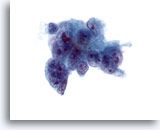

画像 78

膵FNA、膵腺癌

中等度分化型膵癌の吸引組織にみる悪性細胞。合胞化した細胞の集塊を形成し、核の大小不同および核形不整が著明に認められます。

60倍

画像 78

膵FNA、膵腺癌

中等度分化型膵癌の吸引組織にみる悪性細胞。合胞化した細胞の集塊を形成し、核の大小不同および核形不整が著明に認められます。

60倍